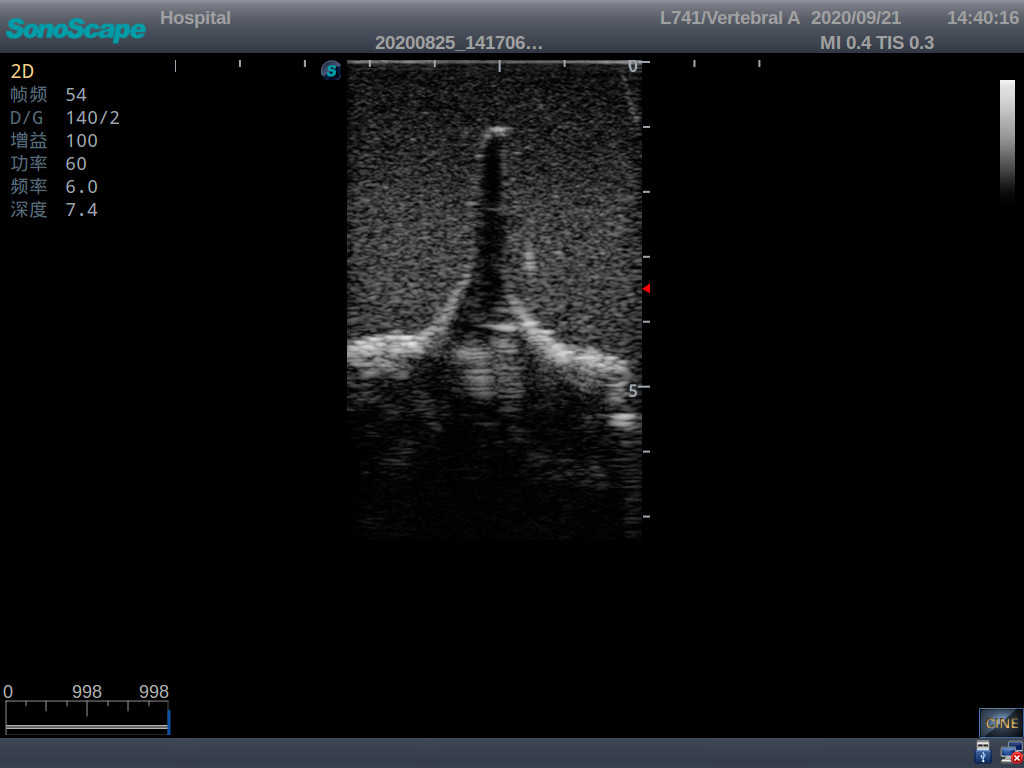

Adult Lumbar Puncture Ultrasound Training Model

Model TYE1549.2

This model is an ideal choice for ultrasound-guided adult lumbar puncture training with true-to-life skin feel and touch, accurate anatomical structures as well as real clinical ultrasound images. Realistic resistance to needle tips and correct landmarks provide excellent hands-on experience.

Accurate anatomical structure of L1-L5 and the vertebral canal

2)  Real clinical ultrasound images

1)   Ultrasound-guided lumbar puncture practice